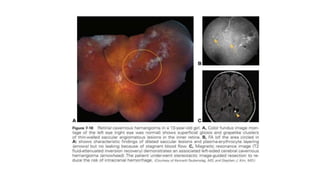

Ret i nal Cavernous Hemangioma

• Reti n al cavernous hemangioma is characterized by the formation of

grapelike clusters of thin- walled saccular angiomatous lesions in the

inner reti na or on the optic nerve head.

• plasma- erythrocyte layering is pathognomonic on the FA.

• Fluorescein leakage is characteristically absent, and serving to

differentiate the condition from reti n al telangiectasia, ret i nal

hemangioblastomas, and racemose hemangioma of the reti na.

• These hemangiomas usually remain asymptomatic but may bleed

into the vitreous in rare instances.

• Treatment of reti n al cavernous hemangiomas is usually not indicated

unless vitreous hemorrhage recurs, in which case photocoagulation

or cryotherapy may be effective.

• Intracranial hemangiomas may lead to seizures, intracranial

hemorrhages, and even death.

• Neuroimaging should always be done to rule out intracranial

involvement.